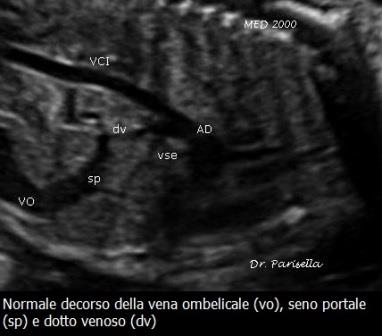

La visualizzazione ecografica della vena ombelicale è quella di un vaso venoso in sede intraepatica che si dirige in alto e posteriormente per poi curvare verso destra dando origine al seno portale.

I rapporti anatomici con le strutture adiacenti, cioè stomaco e colecisti, sono i seguenti: stomaco a sinistra, vena ombelicale al centro con seno portale che curva verso destra, colecisti a destra.